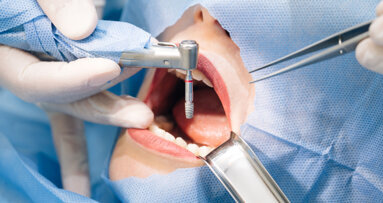

The Bone Growth Concept focuses on the techniques implantologists can implement to preserve a bone without having to resort to the use of any biomaterial. Leading implantologist Dr Zafer Kazak shares his expertise with Dental Tribune UK & Ireland.

Secondly, clinical experience has shown that I can insert almost all of the implants which do not require grafting as flapless. Especially since I started using the copaSKY implant type, which is a Backtaper, I have had the opportunity to improve this way of working because in this way, when I carry out flapless surgeries and place them 2 mm subcrestally, it is possible to use all kinds of superstructure materials at the same time without putting pressure on the bone. In some cases, I can use Er Yag laser to correct excess bone and work flapless in all appropriate cases.